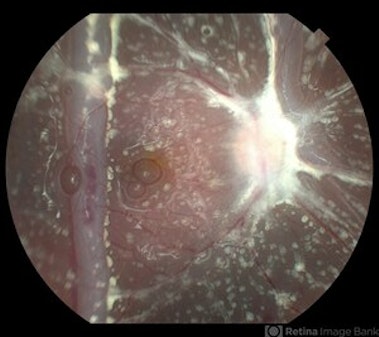

Macular Splint: A Prospective Randomized Study Evaluating Pneumatic (Gas Injection) Prior to Vitrectomy Surgery for Macula-Off Retinal Detachment

Category: Retinal Detachment